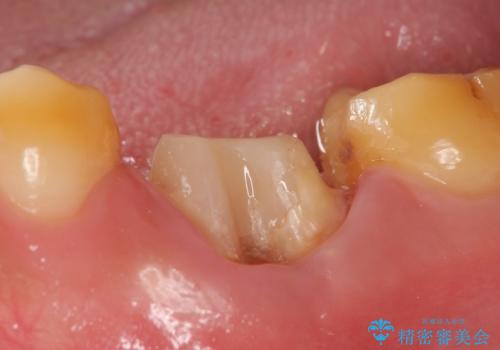

- 咬むと痛む左下6の歯を他院にて診てもらったところ抜歯しかないと言われたが、どうしても残したいと当院にいらっしゃった方の症例です。

検査の結果、根尖病変が大きくポケットも 10mm 以上ありましたが、マイクロ(顕微鏡)にて精査したところ歯根破折は認められなかったため、再根管治療を行いました。